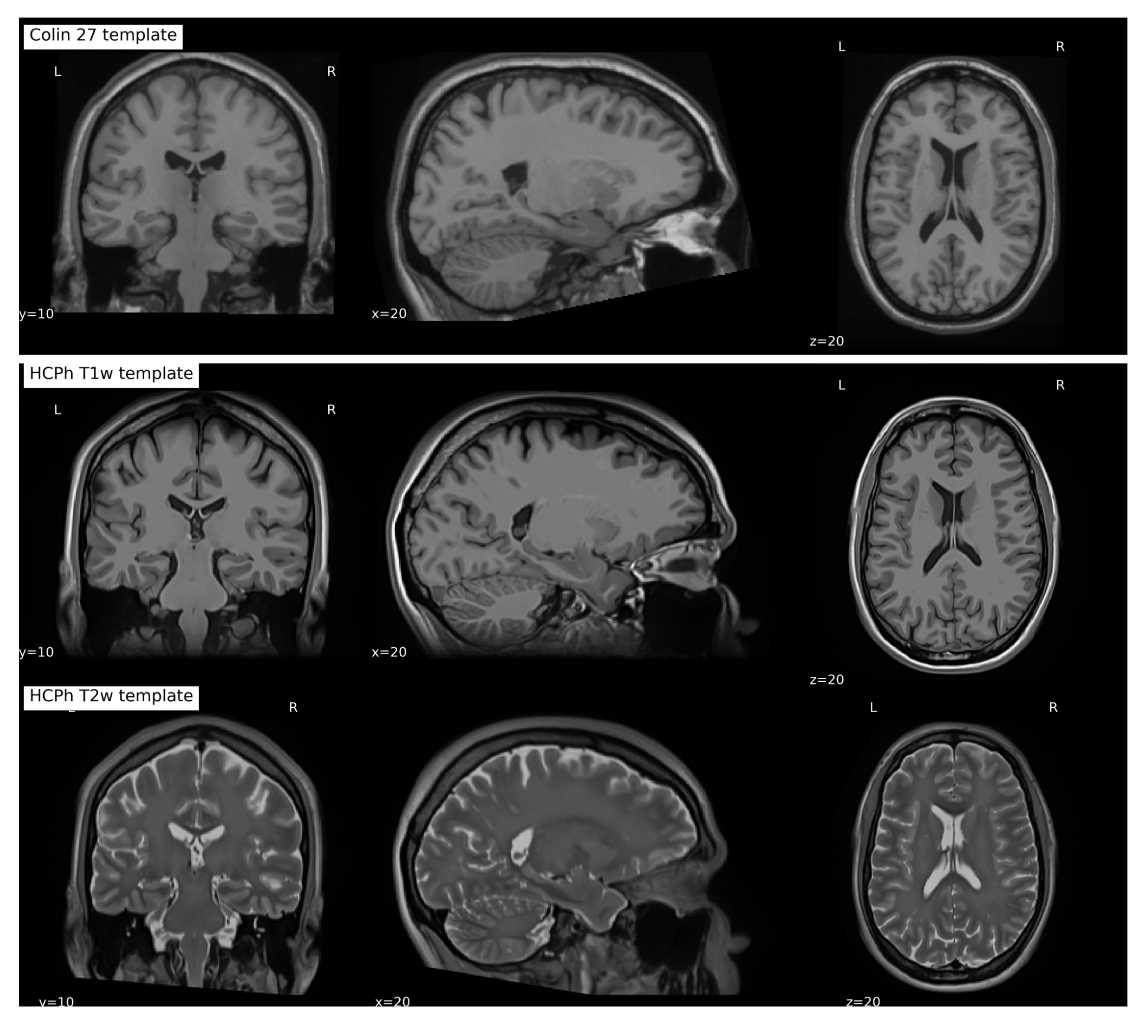

hcph_t1w_template.png

A high definition anatomical brain template of one individual healthy subject

Alexandre Cionca, Yasser Alemán- Gómez, Céline Provins, and 3 more authors

In 30th Annual Meeting of the Organization for Human Brain Mapping (OHBM) in Seoul , Jun 2024